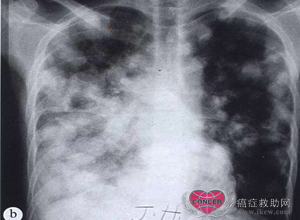

肺转移。(a)一位20岁亚洲男性肝细胞癌患者,胸片示肺内界限清楚的转移性结节。(b)病情在两个月内急剧恶化。虽然肝细胞癌的转移不常见,但也可见转移到骨、肺和脑。